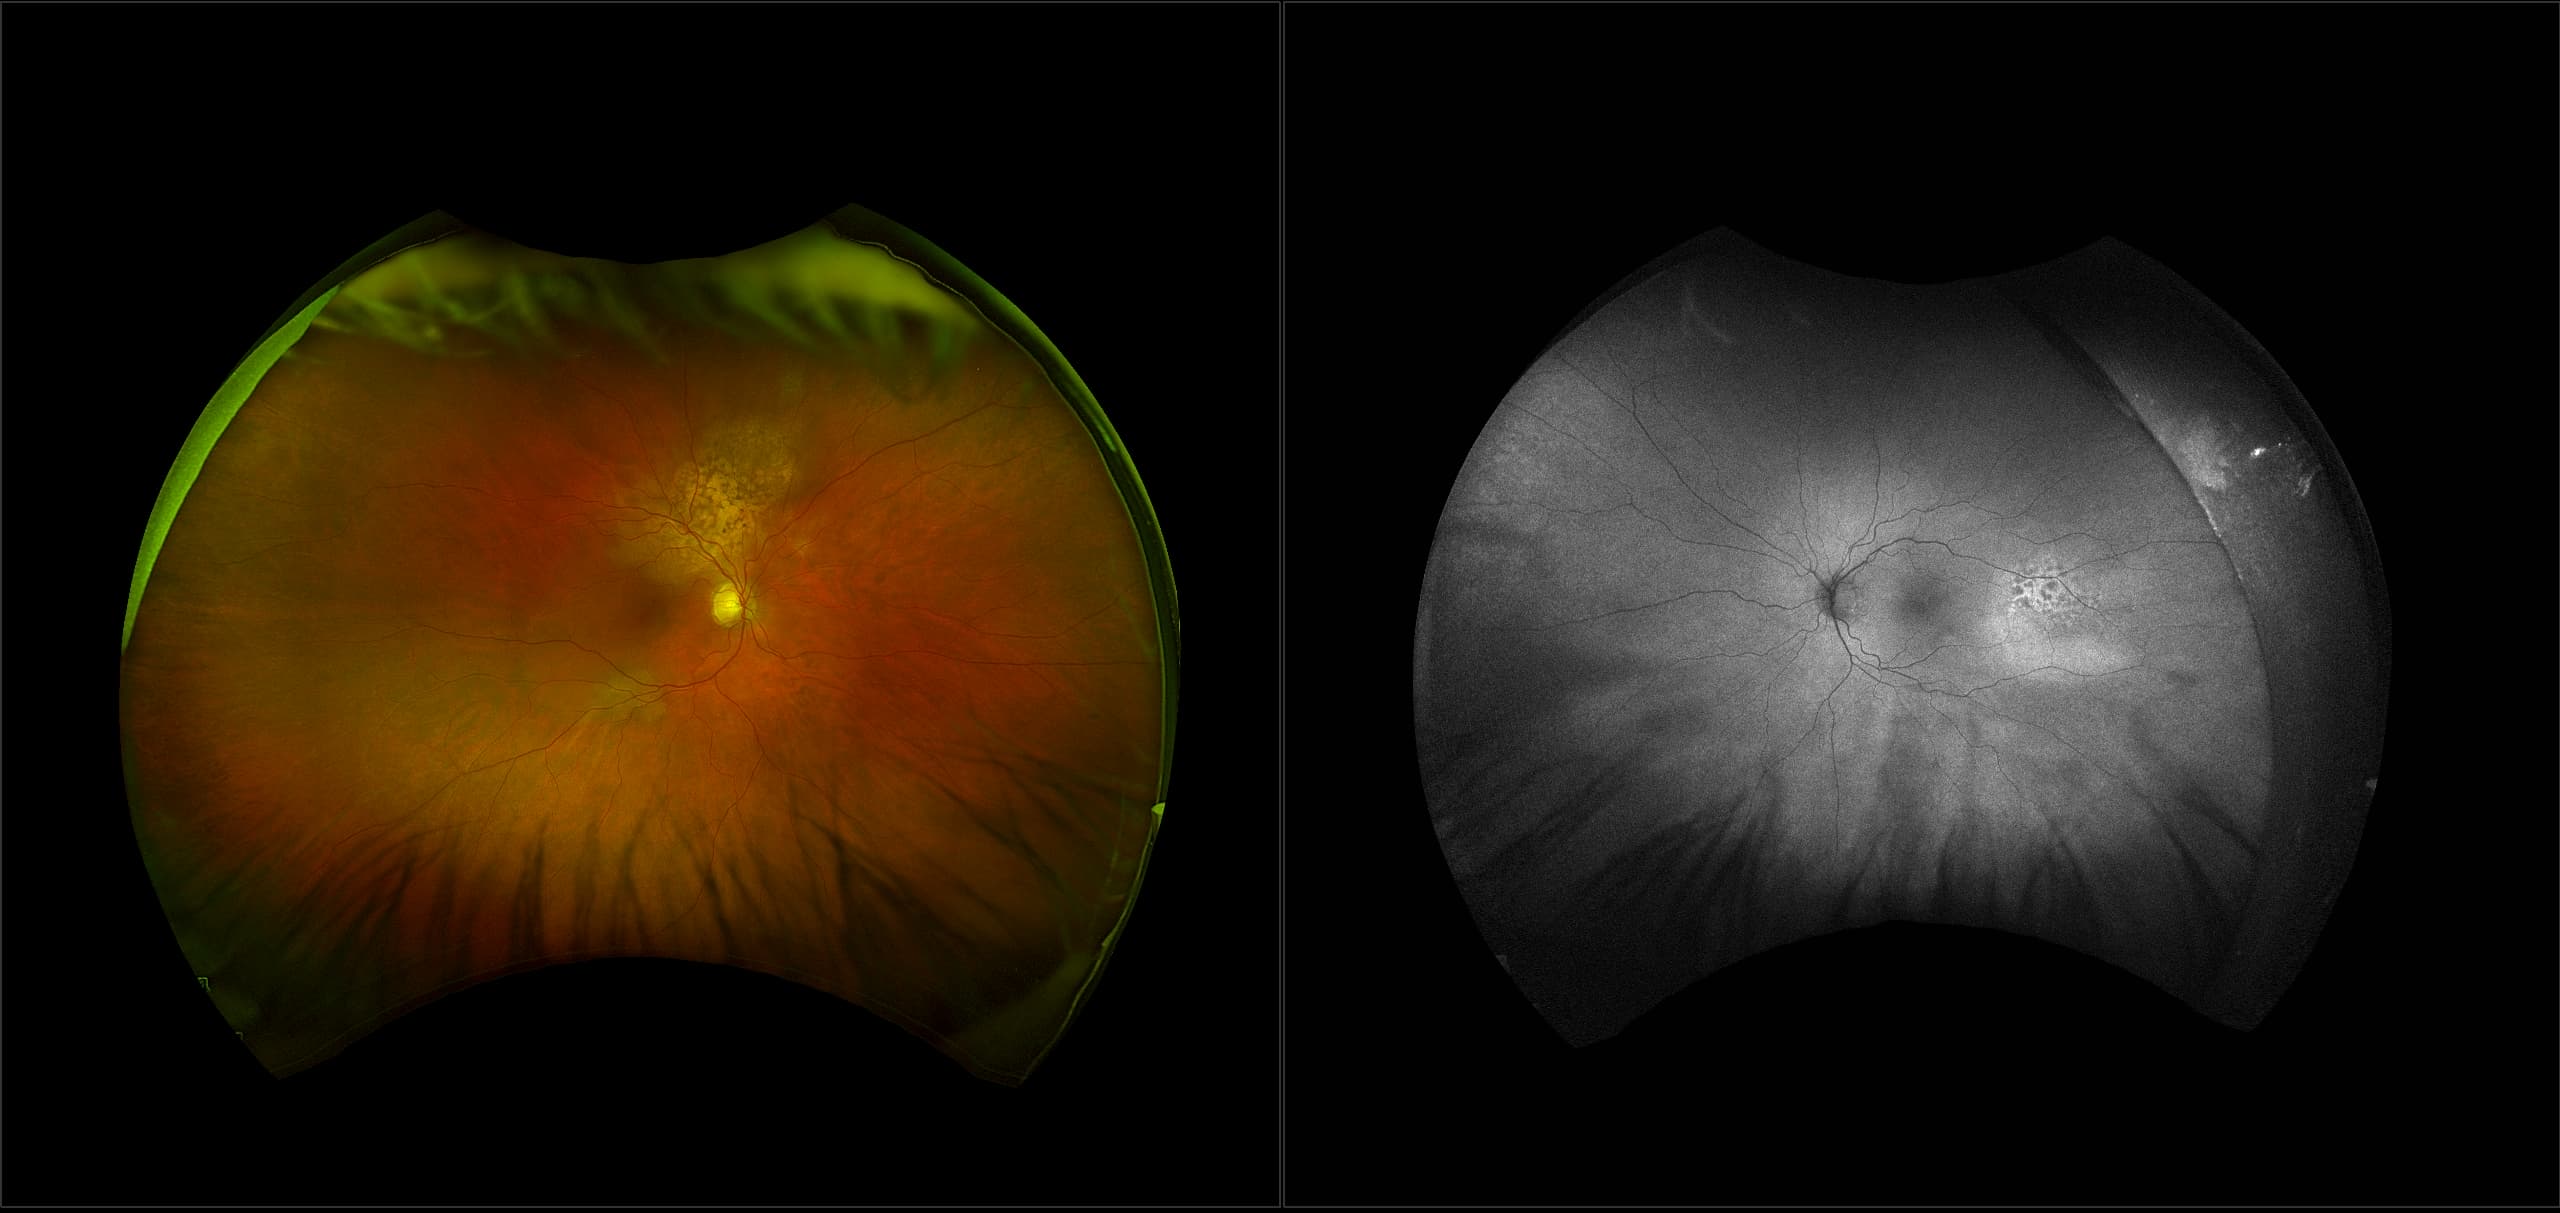

California - Choroidal Nevus, RG, AF

A choroidal nevus is simply an accumulation of melanocytes in the choroid. They are a space occupying mass or a benign melanoma. Choroidal nevi are slate gray in color, have indistinct margins, and may be slightly elevated (1-2 diopters). Since they are in the choroid, they are usually only seen in the red separation and not the green. The green separation may show the RPE degeneration associated with nevi which is seen as pigment mottling and drusen.